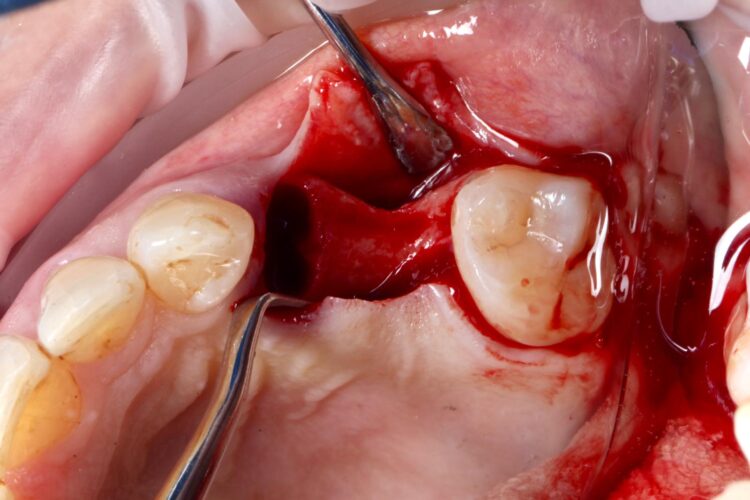

The UL4 root was extracted as atraumatically as possible. The roots were thin and spindly, and needed to be split to be removed safely. They were sectioned in a mesial-distal direction to leave the buccal and palatal roots separate, reducing the risk of fracture and preserving the interdental and surrounding bone.

A flap was raised in the UL5 site using a paracrestal incision – vertical incisions were avoided to preserve blood supply to the gingiva, protecting the papilla between the UL6/7 for optimal aesthetic and soft tissue outcomes.

Technically, a flap is not typically needed for many immediate implant cases. However, as the UL5 site needed augmentation and mild atrophy of the ridge was present. The clinician does not advocate flapless procedures for implant placement due to the need to see the underlying ridge and implant following placement.

The surgical guide was then placed in the mouth and the manufacturer’s specific drilling sequence followed, increasing the osteotomy in size incrementally.